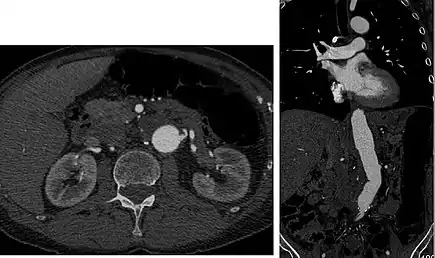

Axial and coronal view of abdominal CT angiography

Aorta and great arteries

CTA can be used in the chest and abdomen to identify aneurysms in the aorta or other major blood vessels. These areas of weakened blood vessel walls that bulge out can life-threatening if they rupture. CTA is the test of choice when assessing aneurysm before and after endovascular stenting due to the ability to detect calcium within the wall.[3] Another positive of CTA in abdominal aortic aneurysm assessment is that it allows for better estimation of blood vessel dilation and can better detect blood clots compared to standard angiography.[4]